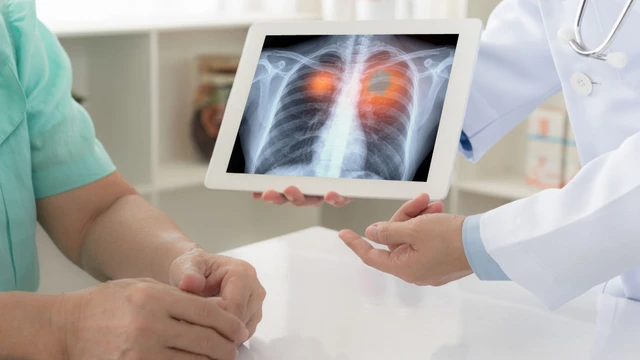

Xơ phổi là một tình trạng y tế nghiêm trọng, xảy ra khi mô phổi bị tổn thương và thay đổi cấu trúc dẫn đến việc mất khả năng cung cấp oxy hiệu quả cho cơ thể. Một trong những phương pháp phổ biến và hiệu quả nhất trong việc phát hiện bệnh là chụp X-quang xơ phổi. Hãy cùng Nhà Thuốc Long Châu tìm hiểu về thông tin này trong bài viết dưới đây.